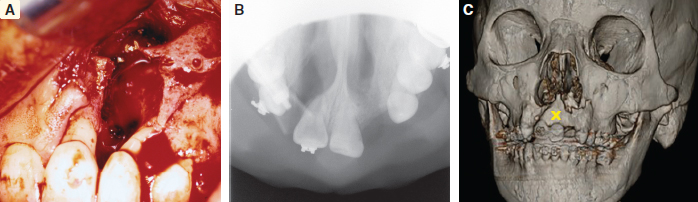

70 ○ Patient selection for alveolar transport distraction osteogenesis and its ultimate success involve patient motivation, parent and patient commitment to the procedure and postoperative course, and excellent oral hygiene. ○ Preoperative planning using three-dimensional imaging and models to execute the projected movements is vital to confirm ultimate segment positioning and stability. ○ Local tissue health and integrity with enough attached gingiva for final “docking” of the distracted segment and bone grafting of the defect is necessary before initiating distraction. ○ The reconstruction team consists of a surgeon, an orthodontist, and a restorative dentist (prosthodontist) who agree on the plan and timing for distraction. ○ Simultaneous anterior maxilla and piriform distraction can be achieved through distraction of a larger dentoalveolar segment, thus augmenting these regions, with or without grafting. Management of the alveolar cleft defect (ACD) has often been a challenging aspect of the comprehensive management of patients with orofacial clefts. The ACD results from intentional delay in treatment or failed attempts at repair during primary cleft lip or palate surgery. Typically, ACDs result in a collapsed, disunited arch with unsupported lip, nasal, and dental elements. The concomitant oronasal fistula (ONF) contributes to sinonasal inflammation, drainage, and periodontitis. Therefore repair of the osseous defect and closure of the fistula are considered important aspects of complete cleft management. Fig. 70-1 A, Right unilateral cleft with wide, disparate alveolar segments. B, Right unilateral cleft with deficient soft tissue and a wide bony defect. Repair of the ACD has a long history in cleft care. The goals for adequate treatment include1,2: Attempts at ACD closure by performing gingivoperiosteoplasty at lip repair have been met with varying results, oftentimes necessitating future formal repair with bone grafts. The timing of ACD repair also has been controversial. Primary osteoplasty, with placement of autogenous bone at or near the time of initial lip repair, has been both condemned and championed. Many results have been less than ideal, again with the need for further bony augmentation of the alveolar segment.3–5 Secondary osteoplasty of the ACD is considered the treatment of choice for many cleft teams, principally because it is predictable and achievable, satisfying the goals of repair as stated previously. Early secondary osteoplasty, as advanced by Boyne and Sands6 as well as others, attempts to graft the ACD before eruption of the permanent incisors.7,8 Delayed secondary osteoplasty has been shown to be effective and predictable for most children when it is performed before the complete root formation of the adult canine tooth, around 10 to 12 years of age.9,10 Delayed secondary osteoplasty is usually performed in conjunction with preparatory orthodontics and after some orthopedic manipulation to optimally position the cleft segment. However, a significant number of patients experience failed bone graft procedures, have very wide defects with collapsed cleft segments, or have significantly scarred ACDs with questionable soft tissue covering, all of which make further attempts at bone grafting rather dubious and unsatisfying. This is aptly termed recalcitrant ACD (Fig. 70-1) and is especially challenging in particular circumstances: a lack of healthy unscarred mucogingival tissue lining the ACD, deficient alveolar bone height and width against which the graft must be placed, older patients with decreased bony healing potential, and the presence of compromised dentition or prostheses with little bone support.11 Recently, distraction osteogenesis (DO) has been developed for application in the craniofacial region. Smaller regional areas of the facial skeleton have been distracted to optimize functional and aesthetic units for future orthopedic or orthodontic correction, grafting procedures, or prosthodontic rehabilitation. In 1905, Codivilla12 initially described the concept of DO to lengthen a femur, correcting a limb length discrepancy. In the 1950s, this application was more widely applied to orthopedic limb lengthening. The landmark research into this technique by Ilizarov13 looked at the development of distraction techniques, devices, and rates on bone formation. He developed the technique on canine long bones and then applied the protocol to human patients, pioneering many of the concepts of DO, including recommendations on latency, distraction rate, and distraction rhythm. In 1992, McCarthy14 applied DO to the unilateral mandibular deficiency found in hemifacial microsomia. He lengthened the affected mandible in children using an external fixation device, which allowed calibrated distraction between external pins holders. At the completion of the distraction phase, the mandibles were stabilized for a mean period of 9 weeks. DO of the midface region has been performed by devices categorized as internal or external devices. Several maxillary DO devices have been used to advance the maxilla through either various osteotomies at the LeFort levels or segmentation of the maxilla.15 These procedures are discussed in Chapters 73 and 74. To achieve maxillary arch widening, Bell and Epker16 used a DO technique of rapid palatal expansion with a tooth-borne expander, increasing the transverse dimension of the maxilla after osteotomies had been performed. Guerrero and Bell17 further developed these techniques, using incremental expansions of 1 mm every other day, up to a total of 10 mm, to obtain significant transverse expansion of the arch. This concept was applied to the alveolar segment by Chin and Toth,18 who looked at regenerating alveolar bone after trauma using an internal distraction device with a transmucosal activation screw. Block and Baughman19 further applied DO to the vertically deficient alveolar segment, increasing bone height before implant placement. Simultaneous secondary bone grafting was performed in many of these cases after final alveolar segment distraction. Use of alveolar distraction is now widespread for preprosthetic manipulation before rehabilitation.20 Cleft alveolar distraction has been performed and studied by Liou et al,21 who used various osteotomies and appliances to approximate cleft segments, narrow the ACD, and improve arch dimension. Others also have applied DO to correct various cleft-related problems, such as a narrow or collapsed maxillary arch and a wide ACD with insufficient soft tissue, and to prevent bone grafting an ACD.22–25 Distraction has become an important tool in the management of particularly difficult or recalcitrant ACDs, discussed later in detail. Several indications for alveolar transport DO exist. A very wide ACD may preclude a bone graft if soft tissue and alveolar bone are deficient (see Fig. 70-1). A patient who has had a previous failed bone graft may be considered for transport DO to achieve the goals of standard alveolar cleft surgery (Fig. 70-2). Older patients who have not been treated for their ACD may be candidates for transport DO to narrow the defect and thus require minimal secondary grafting, improving the success for prosthetic rehabilitation. Fig. 70-2 A, A failed primary osteoplasty with a persistent defect. The failed bone graft was done at age 1. The patient has a fistula and insufficient osseous support for dental structures. B, Partial osteoplasty of a bilateral cleft defect with failure of the graft on the patient’s right. C, A patient with a partial osteoplasty on the left and complete failure on the right side. Alveolar cleft defects are, by nature, multidimensional, and have different defect combinations including the anteroposterior, horizontal, and vertical dimensions. Depending on the specific defect, transport DO may be considered for definitive treatment or to address the largest dimensional deficiency, thereby improving the quality and quantity of alveolar bone. This will allow for an easier and minimal secondary bone graft procedure. This process is particularly applicable when treating vertical alveolar deficiency. Vertical alveolar DO may be considered to increase alveolar bone height after grafting and when planning placement of an implant for later prosthetic rehabilitation. Several contraindications to alveolar cleft DO exist. A surgeon should be wary of initiating alveolar DO for patients with clefts who have not been compliant in various aspects of their treatment. DO is a very labor-intensive process, requiring a great deal of cooperation from the patient and caregivers; therefore education is crucial before initiating treatment. Patients with active dental issues should have these addressed, with consideration given to optimizing oral health before surgery. Periapical disease should be eliminated to prevent infection during the distraction period. In patients younger than 10 years of age, the potential exists for damage to developing teeth and impairing the eruption pattern in the area of distraction. This needs to be thoroughly discussed with the patient and family beforehand. Indirectly associated with compliance are the patient’s general health and condition of the local tissues. If any concern exists related to these areas, avoiding this mechanically technical procedure and the potential subsequent complications of tissue breakdown and loss of the device may be prudent. Children who have poorly controlled chronic asthma or allergies, resulting in nasal obstruction and patterns of mouth breathing that increase oral tissue inflammation, may be prone to intraoral tissue compromise and breakdown. For these reasons, optimal intraoral health should be maintained through primary care and pediatric dental management. Once these concerns have been satisfied, then plans for distraction can be undertaken. Fig. 70-3 An acrylic model of a right unilateral cleft defect (X) demonstrating planned distraction of the alveolar segment (arrow). As with all aspects of comprehensive cleft care, management of the ACD benefits from a team approach. Preparing the patient and family for the various aspects of therapy is important before initiating alveolar transport DO. In addition, coordination of the team involved in perioperative management is essential. The patient’s pediatric dentist should be involved well before transport DO is considered to optimize oral health before surgery. Any carious lesions should be addressed and periodontal disease eradicated before the patient is assessed for surgery. Questionable or nonvital teeth should be treated before DO is begun to eliminate the possibility of infection jeopardizing the distraction process. Orthodontic consultation and management is important to address dental and arch discrepancies before the repair of the ACD, whether by conventional bone grafting or by movement of the alveolar bone using distraction. The arch may require expansion before formal repair of the alveolar cleft, and the orthodontist must be involved in the planning and management during distraction. Finishing dental and arch alignment is the orthodontist’s responsibility. Prosthodontic management of the patient may be required postoperatively for the replacement of missing teeth. This may involve the placement of crowns or bridges, or the surgical placement of implants if bone stock is adequate. The patient must appreciate that grafted bone must be completely mature before implants can be placed, a period of approximately 3 months.26 Consultation with the prosthodontist is important to evaluate the arch space and bone height that will be needed for prosthetic rehabilitation. Three-dimensional acrylic models (Fig. 70-3) are a great help to the treating team, patient, and caregivers who will be involved in the distraction process. Precise placement and activation of the device can be achieved and demonstrated. The caregivers need to be instructed in the cleansing and hygiene of the activation rod. Perioperative antibacterial mouth rinses (oral chlorhexidine) and oral antibiotics should be carefully reviewed and dispensed. Pain medications and dietary instructions will need to be adjusted based on individual patient needs. Most children will have adequate analgesia with ibuprofen, which may be administered before or after each distraction event, as indicated. It is important to instruct the patient and caregivers about the objectives of DO and to create realistic expectations for what can be achieved. Instructions for care may have to be given in stages and over several preoperative appointments to establish a thorough understanding before and during treatment. The patient and family need to appreciate that DO may not be able to completely correct the anatomic deficits. Further surgery, in a second stage, will be required to remove the distractor; at that time, the defect can be simultaneously augmented with additional bone graft if necessary. As in many ACD reconstructions, final and acceptable soft tissue coverage may be required in a separate procedure to provide adequate attached gingiva around the teeth and implants. Vital to the success of any intraoral surgical procedure, particularly around the dentition and any abnormal anatomy, is optimal soft tissue composition and health. Loss or limitation of healthy keratinized tissue around the dentition may compromise the general integrity of the periodontium, leading to further bone loss or predictable bony surgery in the future. Studies have demonstrated that patients with cleft lip or palate have more periodontal compromise in the cleft defect area, including loss of a zone of healthy keratinized tissue.27,28 Although loose (unattached) mucosa may serve as a temporary healing or covering measure, such as labiobuccal mucosa grafts placed during primary or early secondary osteoplasty, this does not serve well for periodontal integrity in the long term. If plans are made for segmental osteotomy or distraction of a cleft segment, healthy abutting transposed attached (keratinized) tissue, both palatally and labiobuccally, is preferable. Soft tissue inadequacies such as these are seen especially in older cleft patients who have undergone multiple procedures, resulting in compromised soft tissue in and around the alveolar cleft defect and dentition.29 If a lack of healthy soft tissue is determined during the evaluation process, then plans should be made to graft the area to provide this tissue. Autologous graft from the palate (preferred) or acellular dermis graft can be placed in the immediate defect area and periodontium.30 After a period of maturation, variably 8 to 12 weeks, when keratinization is complete and inflammation resolved, subsequent bony surgery can be undertaken. When juxtapositioning the alveolar segments during final distraction, flap elevation and coverage of the bone graft should be easier and final closure more predictable with appropriately healthy mucogingiva. Unilateral ACDs are more common and often have problems with significant asymmetry and excessive defect width. Although skilled interceptive orthodontics can often successfully align and position the lesser segment and narrow the defect width, occasionally the poorly positioned cleft segment will remain, with suboptimal soft tissue that would compromise, and potentially prohibit, orthodontic treatment. A typical case is illustrated in Fig. 70-4. This patient had a long history of cleft surgical procedures, as well as two phases of orthodontics. The ACD was still poorly positioned with extensively scarred soft tissue; the radiographs verified a significant bony defect width between the segments. This situation is difficult to correct with conventional orthodontic preparation and alveolar bone grafting; therefore distraction of the cleft segment, to narrow the defect by approximating the alveolar segments, will increase the success of a smaller bone graft. A single vector alveolar distractor was placed on the buccal aspect of the lesser segment after vertical osteotomy between the bicuspids and horizontal osteotomy, approximately 7 to 8 mm above the level of the root apices. The activating rod is oriented in a favorable position under the lip for easy access. Postdistraction photos demonstrate an alveolus more favorably positioned for bone grafting. Many alveolar distractors offer various distracting lengths (10 to 20 mm) and multiple options for plate and screw placement (Fig. 70-5). The device should be contoured to the alveolar surface so that activation will move the segment in the desired direction. Some distractors allow for orientation of the activation rod from 0 degrees (coaxial to the distractor) to 30 degrees to allow favorable rod positioning and access for daily activation. Minimal activation should be performed during the surgical procedure to prevent undue tension on the overlying soft tissue, which may tear and compromise vascularity. Two or three millimeters of activation, to confirm complete mobility of the osteotomized segment, will suffice at the time of distractor placement.